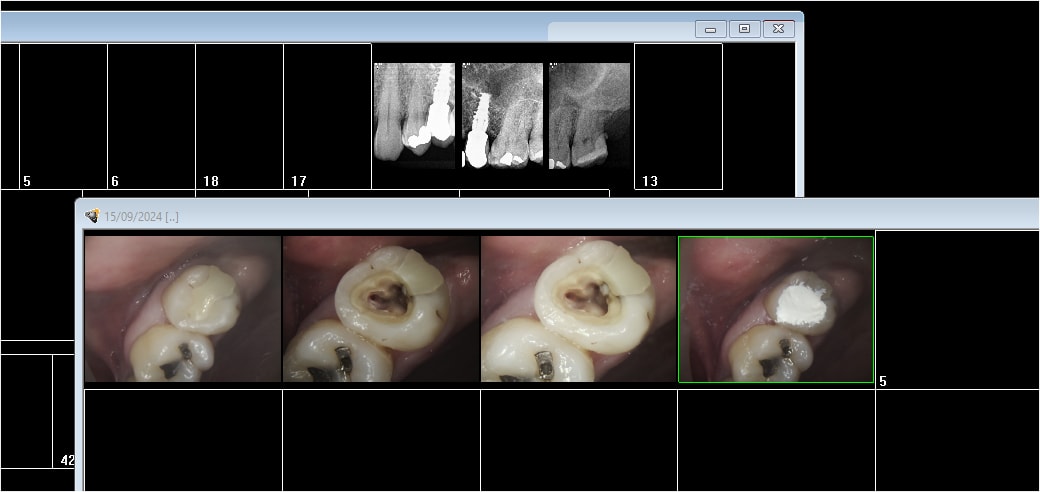

15/09/2024 à 14h32

De garde ce matin belle tuméfaction probablement due à un pro de l'endo minute et de l'amalgame au pouce. La patiente vient d'arriver dans le coin et n'a toujours pas trouvé de dentiste.

15/09/2024 à 14h36

Et 2 pulpites après tentative de conservation de la vitalité pulpaire. C'est curieux j'ai jamais ce genre de problèmes faut dire que j'ai le réciproc facile. -)